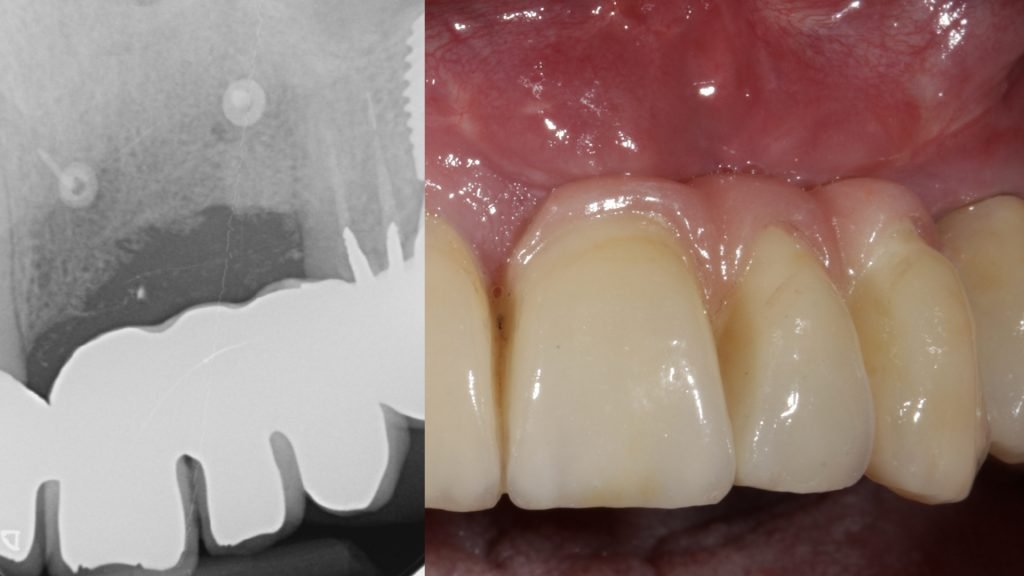

A la exploración radiográfica se observa la pérdida ósea interproximal de los 3 implantes confirmándose así el diagnóstico de periimplantitis (Figura 2).

Trascurrido el periodo de cicatrización, se realizaron las pruebas protésicas pertinentes y se colocó la prótesis definitiva (Figura 16).

Después de 12 meses de seguimiento se puede constatar el mantenimiento del resultado obtenido de forma satisfactoria tanto a nivel clínico, sin complicaciones biológicas ni mecánicas, como por parte del paciente (Figura 17).